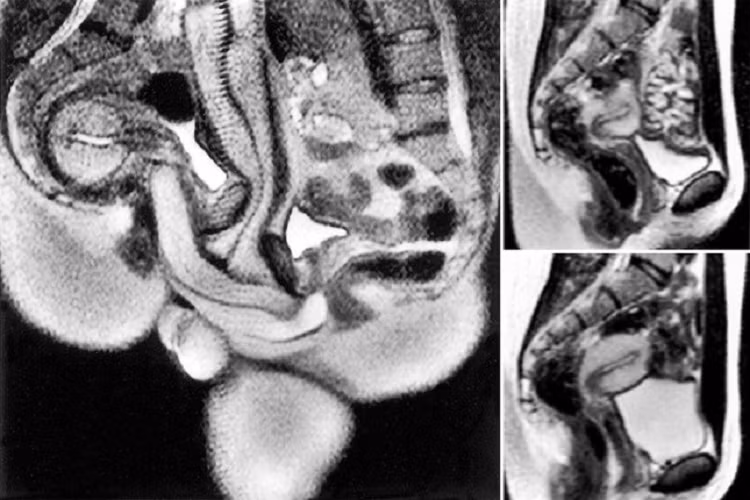

| Quá trình quét cho thấy "cậu nhỏ” có hình dạng của một chiếc boomerang khi làm “chuyện ấy” |

Ida và Jupp đã được kiểm tra thể chất bên trong máy chụp cộng hưởng từ sau khi bạn của họ, nhà khoa học người Hà Lan Menko Victor “Pek” van Andel, bắt đầu khám phá những gì xảy ra bên trong cơ thể chúng ta khi làm “chuyện ấy”.

Những hình ảnh này đã trở thành tâm điểm của một mục cực kỳ nổi tiếng trên Tạp chí Y học Anh (BMJ) vào năm 1999. Giờ đây, sự quan tâm đã được khơi dậy trở lại do câu chuyện và những hình ảnh đang lan truyền trên TikTok dựa trên một bài báo năm 2019 từ Vice .

Thế nhưng, kết quả chụp cộng hưởng từ cho thấy “cậu nhỏ” có hình dạng của một chiếc boomerang, nghĩa là nó uốn cong vào bên trong theo hình dạng của cơ thể phụ nữ mà không gây đau đớn cho người đàn ông khi cương cứng.

Phát hiện này rất lớn, dẫn đến một nghiên cứu chính thức được thực hiện từ năm 1991 đến 1999 bởi Ida và Pek, kết quả của chúng đã được công bố trên tạp chí y học nổi tiếng của Anh BMJ.